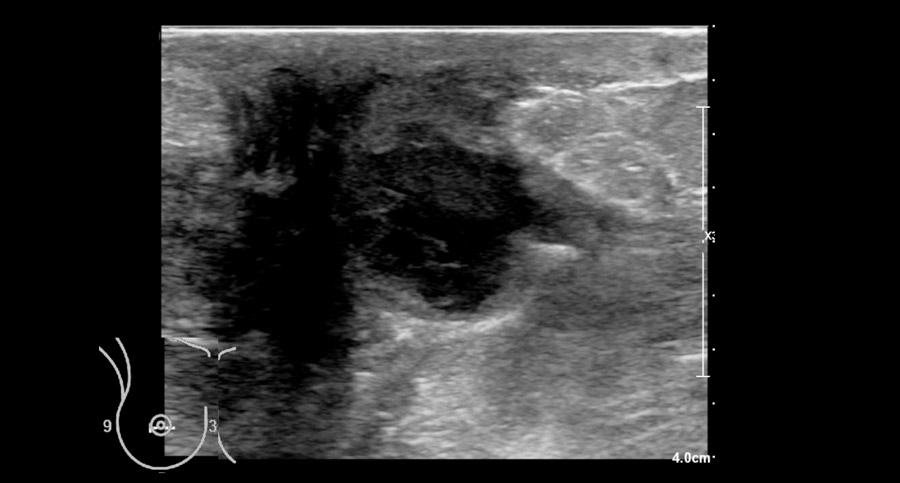

Áp-xe

Áp-xe vú là tình trạng tích tụ mủ gây đau trong tuyến vú do nhiễm khuẩn.

Bệnh chủ yếu ảnh hưởng đến phụ nữ đang cho con bú như một biến chứng của viêm vú và ít gặp hơn ở phụ nữ không cho con bú.

Bệnh nhân thường đến khám với triệu chứng khối đau, da vùng tổn thương có thể đỏ và dày lên.

Hình ảnh siêu âm của một phụ nữ đến khám với triệu chứng sốt và khối đau ở vú phía sau núm vú bị thụt vào.

Trong quá trình ép và thả nhẹ bằng đầu dò, có thể quan sát thấy dịch trong ổ áp-xe di chuyển.

Cũng cần lưu ý hiện tượng tăng âm phía sau (posterior enhancement) — đây là dấu hiệu cho thấy cấu trúc này chứa dịch.

Tiếp tục xem hình ảnh tiếp theo…

Sau đó, ổ áp-xe được tiến hành chọc hút.

Chọc hút là phương pháp điều trị ưu tiên hàng đầu đối với áp-xe.

Trong trường hợp này không cần phẫu thuật hay kháng sinh, mặc dù đôi khi kháng sinh cũng được chỉ định kết hợp.